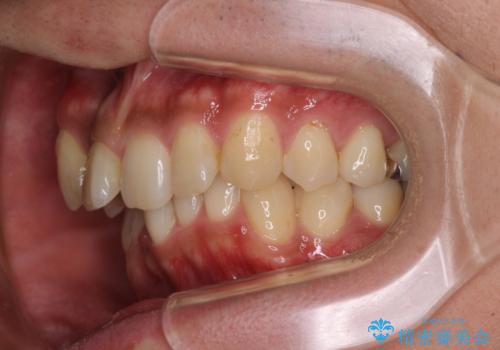

【モニター】八重歯と正中のずれた歯列 片顎抜歯のワイヤー矯正

- 上顎の八重歯と正中のズレを気にして来院された患者様です。

八重歯による叢生は著しく、それにより上顎の正中が大きく右にずれている状態でした。

口元の突出感は感じていなかったことと、奥歯の咬み合わせを考慮し、上顎のみ左右の第一小臼歯を抜歯してワイヤー装置にて矯正治療を行うこととしました。

補助装置を併用することで効率的に八重歯や正中位置の改善を達成することができました。